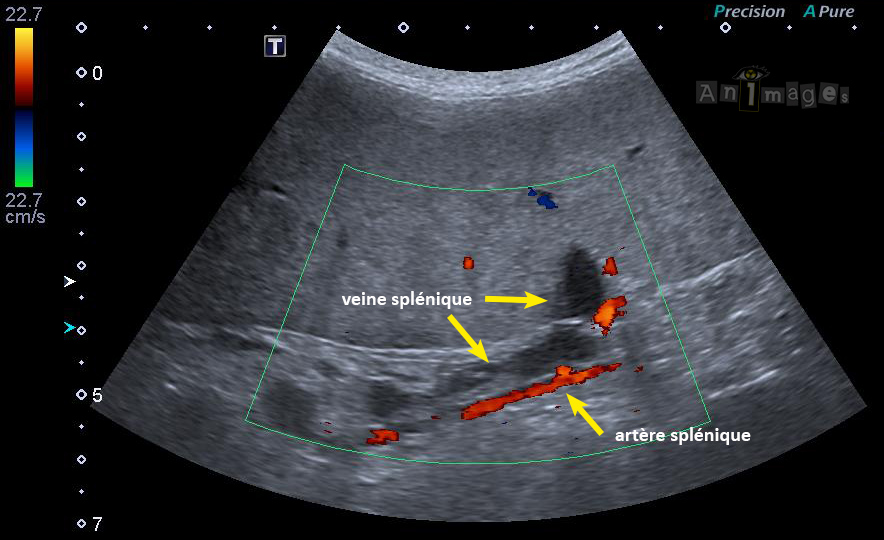

Flux réduit veine splénique

Doppler Couleur